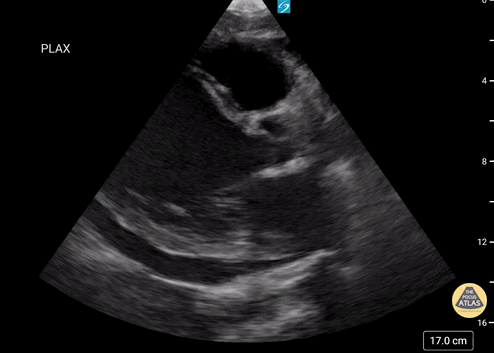

Parasternal uzun aks

Sol ventrikül fonksiyonunun değerlendirilmesi

Sol ventrikül (LV) fonksiyonu dört pencerenin tamamında değerlendirilebilir; ancak genellikle parasternal uzun aks görüntüsünde en kolay şekilde incelenir. Değerlendirme iki şekilde yapılabilir:

Görsel (subjektif) tahmin

EPSS (End Point Septal Separation) ölçümü

Çok sayıda çalışma, acil hekimleri ile kardiyologlar arasında global kardiyak fonksiyonun görsel değerlendirilmesi açısından yeterli uyum olduğunu göstermiştir.

RUSH muayenesinde genellikle ejeksiyon fraksiyonunun tam yüzdesine odaklanmak yerine, sol ventrikül fonksiyonunu geniş kategoriler halinde sınıflandırırız:

Hiperkinetik (hiperdinamik)

Normal

Azalmış (düşük)

Azalmış sol ventrikül fonksiyonunu düşündüren hızlı ve pratik bulgular şunlardır:

Sol ventrikül kavite çapının sistolde yaklaşık üçte bir oranında küçülmemesi

Miyokardın sistol sırasında yeterince kalınlaşmaması

Mitral kapağın ön yaprağının diyastolde septuma yaklaşmaması

Buna karşılık hiperdinamik bir kalpte, sistolün zirvesinde ventrikül duvarlarının neredeyse tamamen kollabe olup birbirine temas ettiği izlenir.